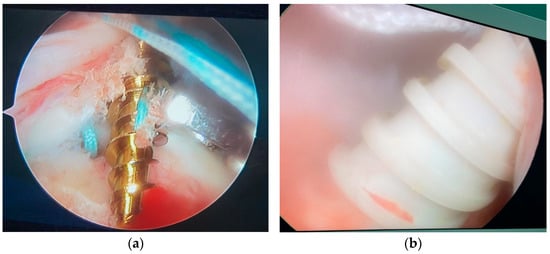

Figure 1.

(a) Intraoperative metallic suture anchor pullout; (b) intraoperative polyetheretherketone suture anchor pullout.